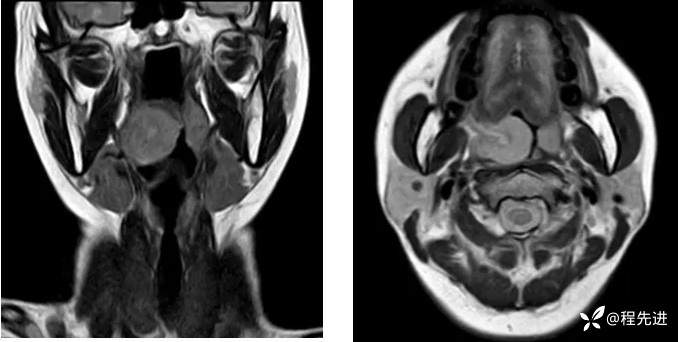

T2: